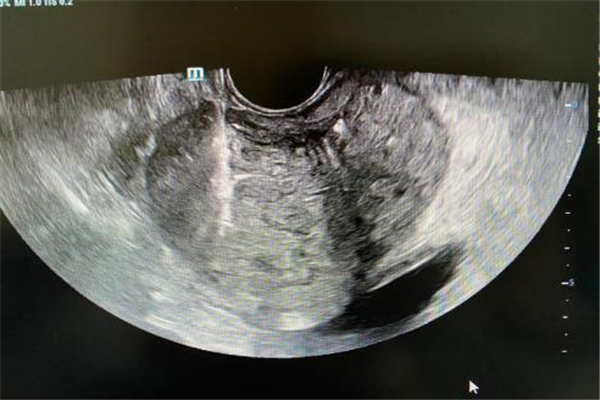

如何早期診斷前列腺癌至關(guān)重要。前列腺癌可以表現(xiàn)為排尿困難、尿頻、尿流弱或中斷,無(wú)法站立排尿,直腸有壓迫感或疼痛等等,與前列腺炎和前列腺增生相似?,F(xiàn)階段隨著醫(yī)療技術(shù)的發(fā)展和水平的提高,超聲引導(dǎo)下經(jīng)直腸前列腺穿刺活檢技術(shù)的應(yīng)用,對(duì)疑似的患者進(jìn)行穿刺病理診斷已經(jīng)成為前列腺癌的主要診斷方法。

超聲引導(dǎo)下經(jīng)直腸前列腺穿刺活檢術(shù),由于安全簡(jiǎn)便、穿刺準(zhǔn)確性和成功率高,在臨床上已廣泛應(yīng)用。自2020年8月起,我院超聲醫(yī)學(xué)科底已經(jīng)成功穿刺15例,陽(yáng)性率高,為前列腺分級(jí)、分期提供病理依據(jù)及臨床選擇治療方案提供重要參考。